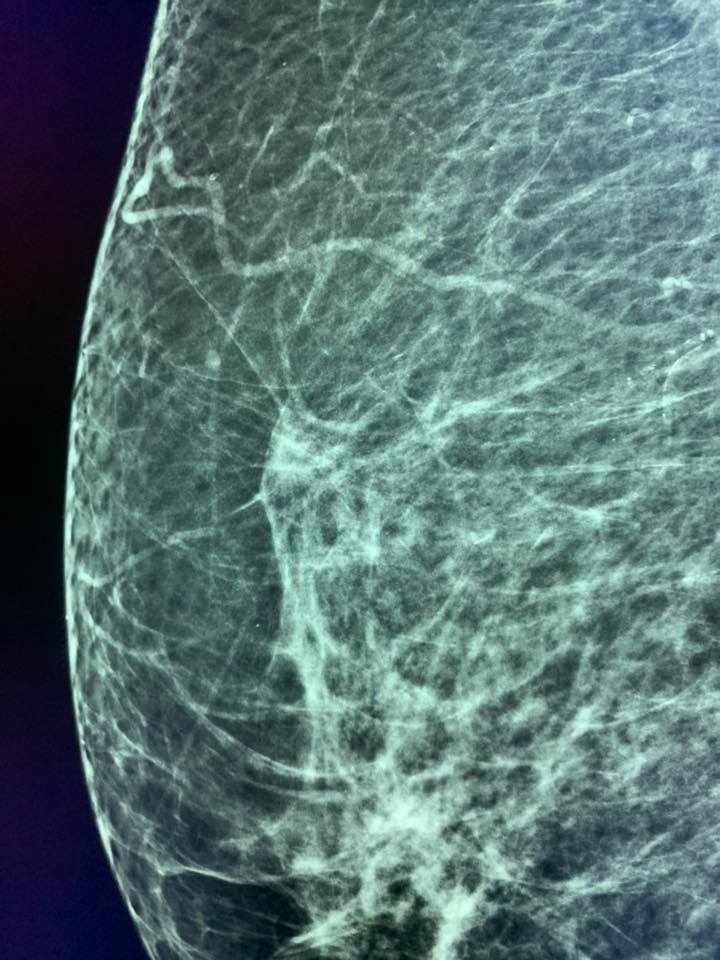

A 73-year-old woman had breast screening. Two years before her screening mammogram was considered normal by two readers.

At first glance, the new breast mammography was also considered as normal and unchanged compared to the prior but MammoScreen™ pointed at a lesion on the right breast.

The retrospective analysis of the prior by MammoScreen pointed at the same area.